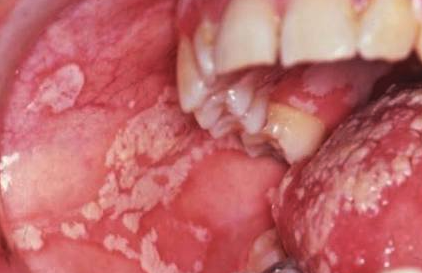

입안에 하얀 백반창(thrush)이 생김.